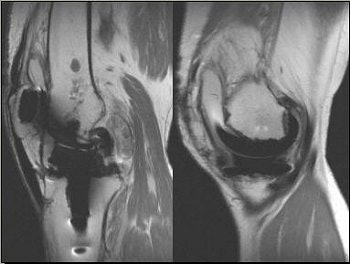

![]() |

| Edema in MCL from osteochondritis dissecans (OCD) and chrondomalacia. |